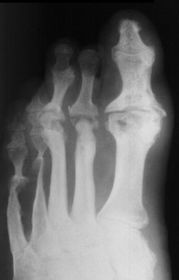

| Describe the alignment of metatarsal 2 | There is no angulation nor displacement of the distal segment relative to the proximal segment. |

| Describe the alignment of metatarsal 3 | The distal segment is displaced laterally (50% apposition) and angulated medially. |

| Describe the alignment of metatarsal 4 | The distal segment is displaced laterally (75% apposition) but there is no apparent angulation. |

| Describe the tubulation of the metatarsals | Metatarsals are overtubulated - decreased girth. |

| Describe the tubulation of the metatarsals | Metatarsals are undertubulated - increased girth. |